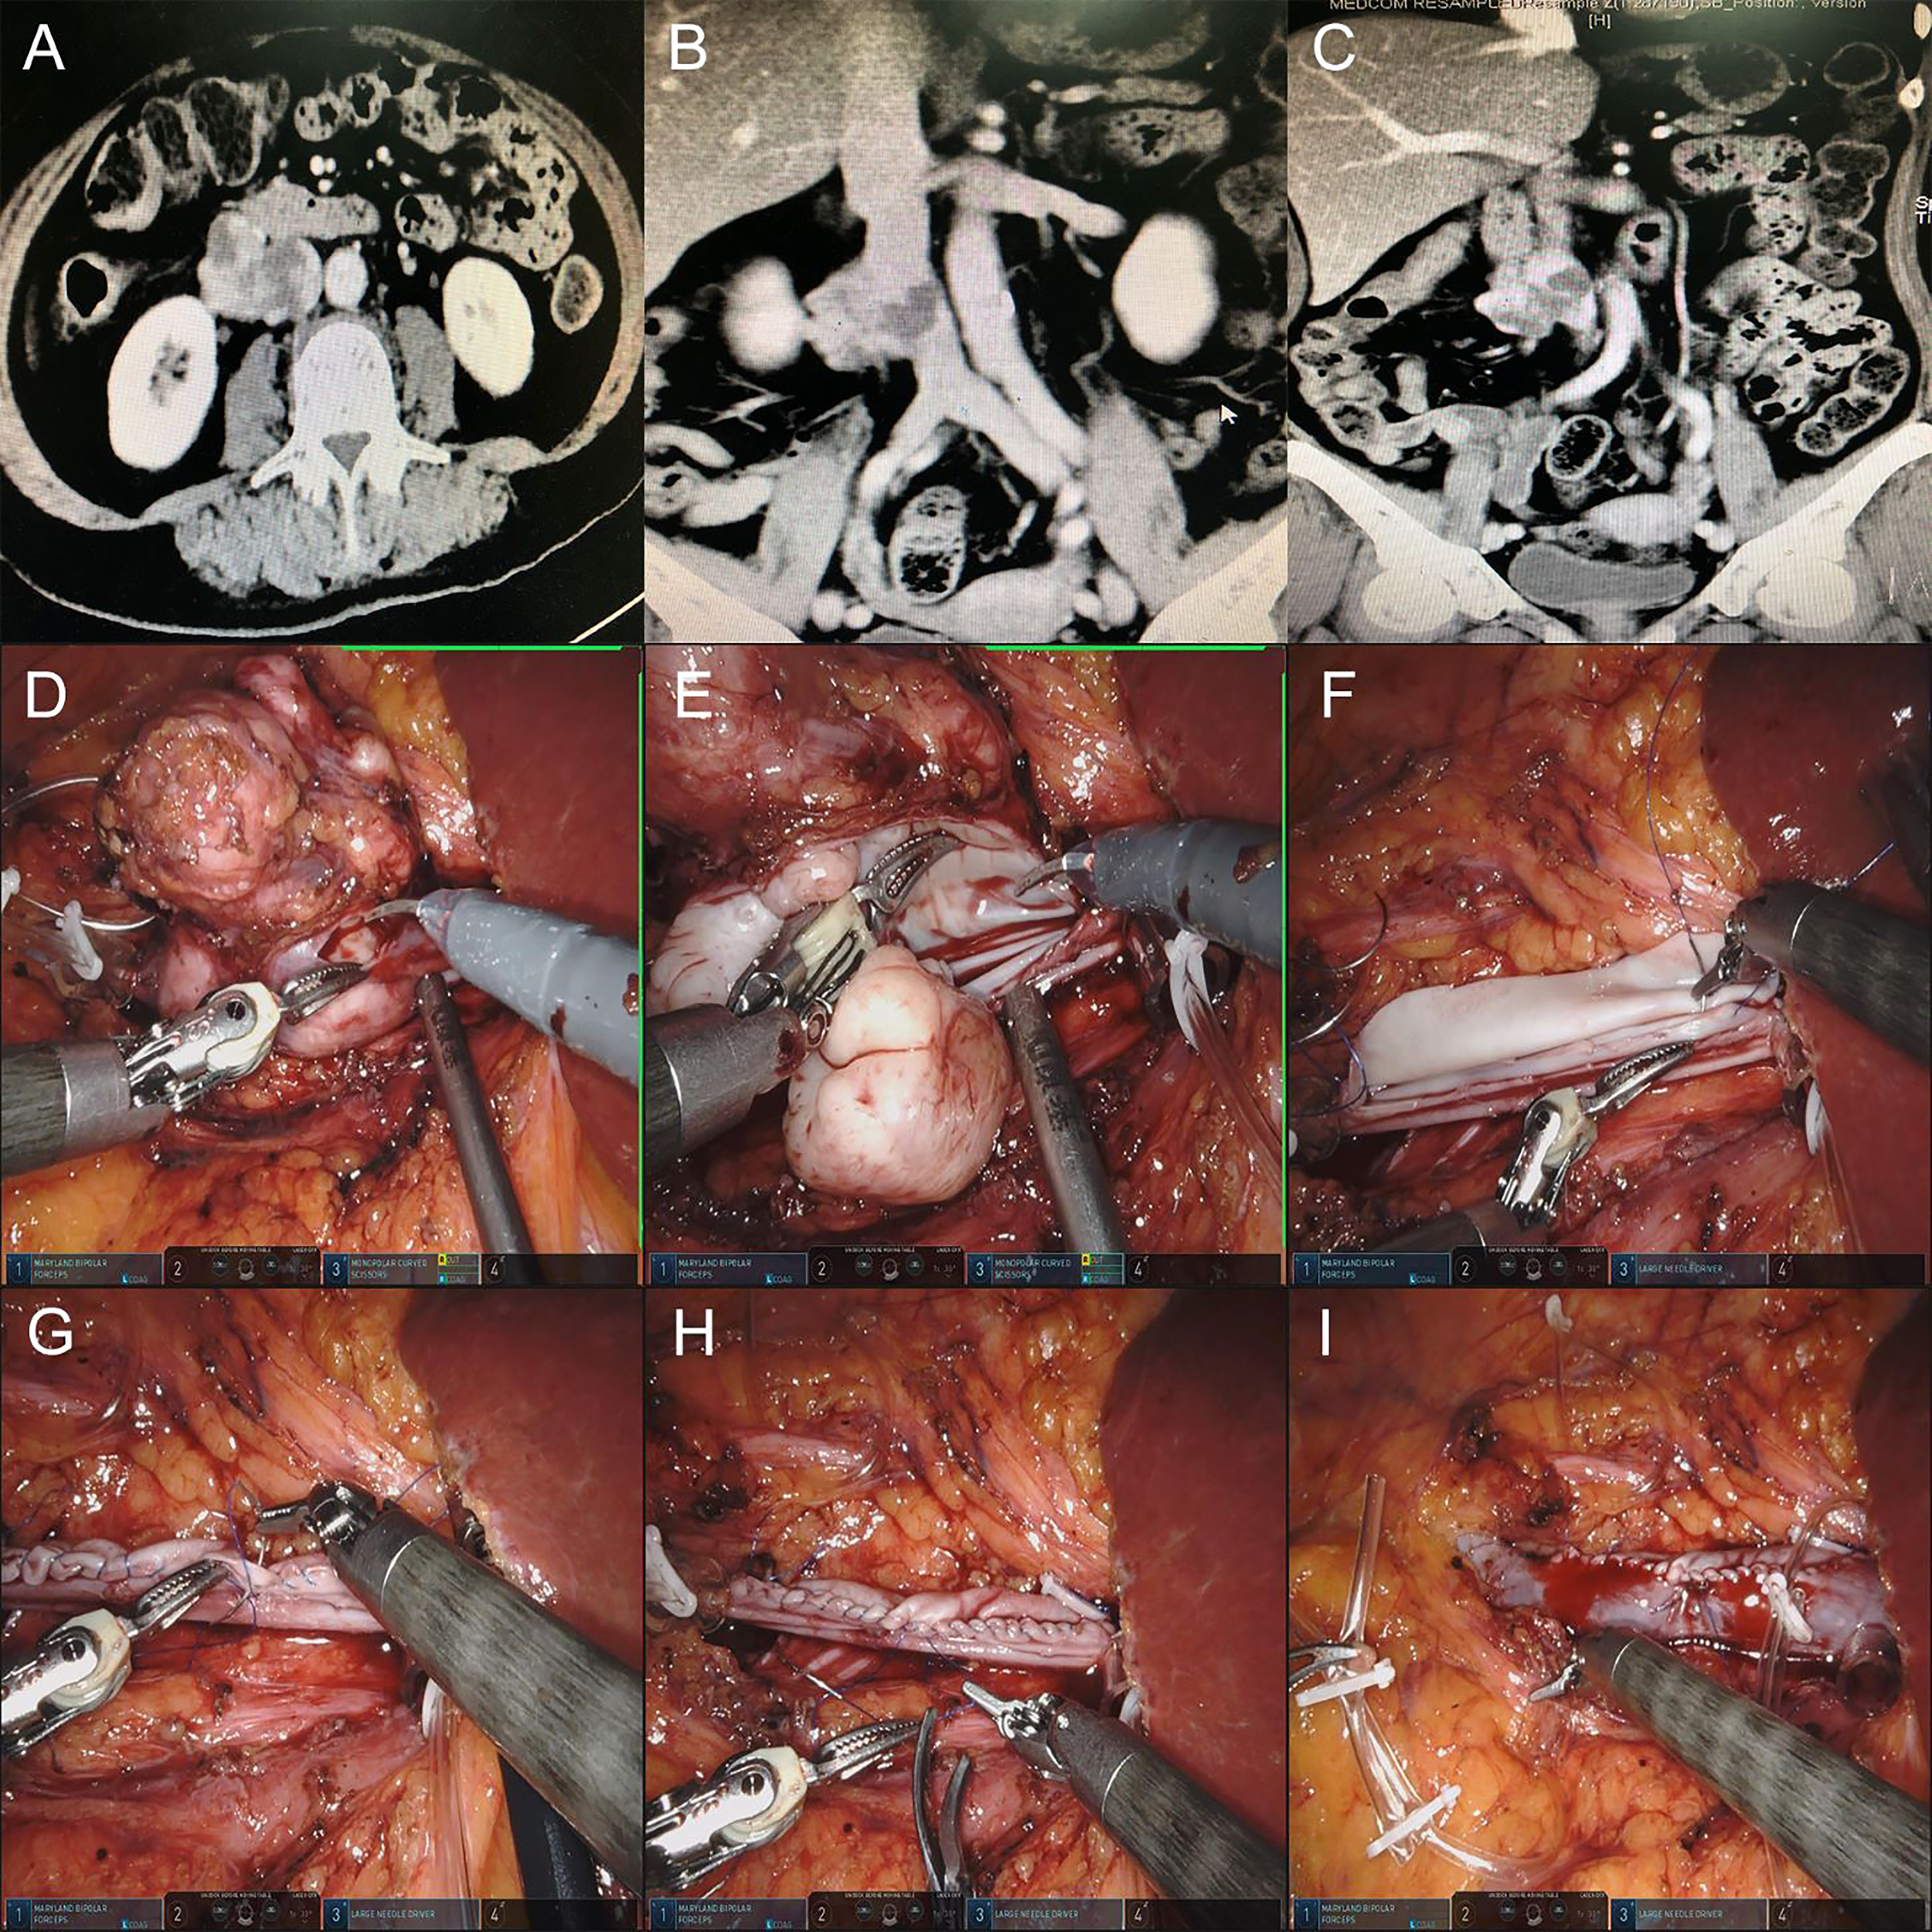

Figure 2

(A–C) Preoperative CTU images of the retroperitoneal tumor of patient 4. (D, E) Resection of retroperitoneal tumor and IVC tumor thrombus. (F) Suture the posterior wall of bovine pericardium graft and IVC wall continuously first. (G, H) Suture the anterior wall of bovine pericardium graft and IVC wall continuously. (I) Release the blocking of the IVC, and the IVC blood flow was unobstructed.